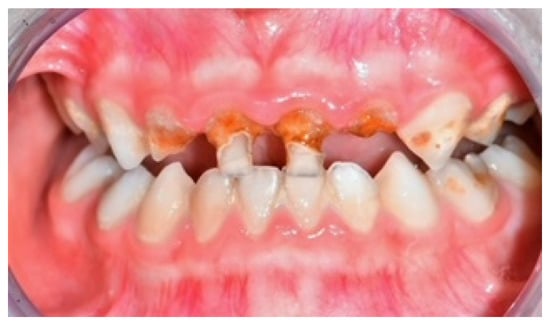

- Cheng, R.; Yang, H.; Shao, M.; Hu, T.; Zhou, X. Dental Erosion and Severe Tooth Decay Related to Soft Drinks: A Case Report and Literature Review. J. Zhejiang Univ. Sci. B 2009, 10, 395. [Google Scholar] [CrossRef]